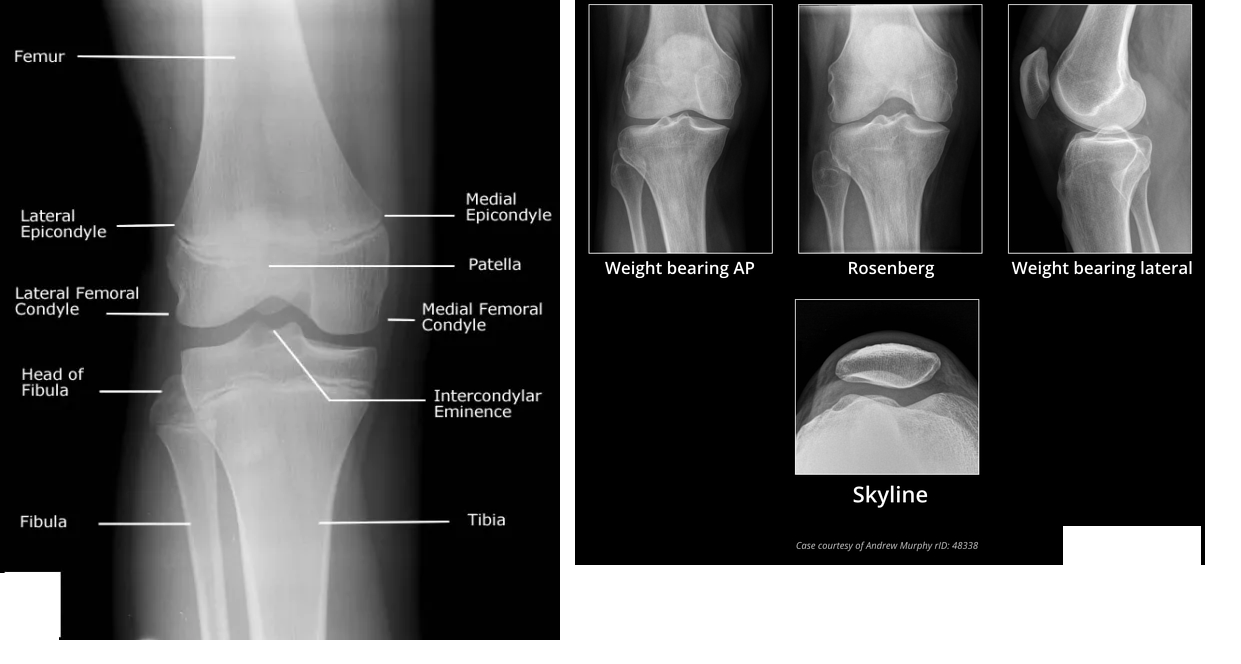

Figure 2: Knee X-rays illustrating a tibial plateau fracture.

Figure 1: Diagrammatic representation of the tibial plateau anatomy.